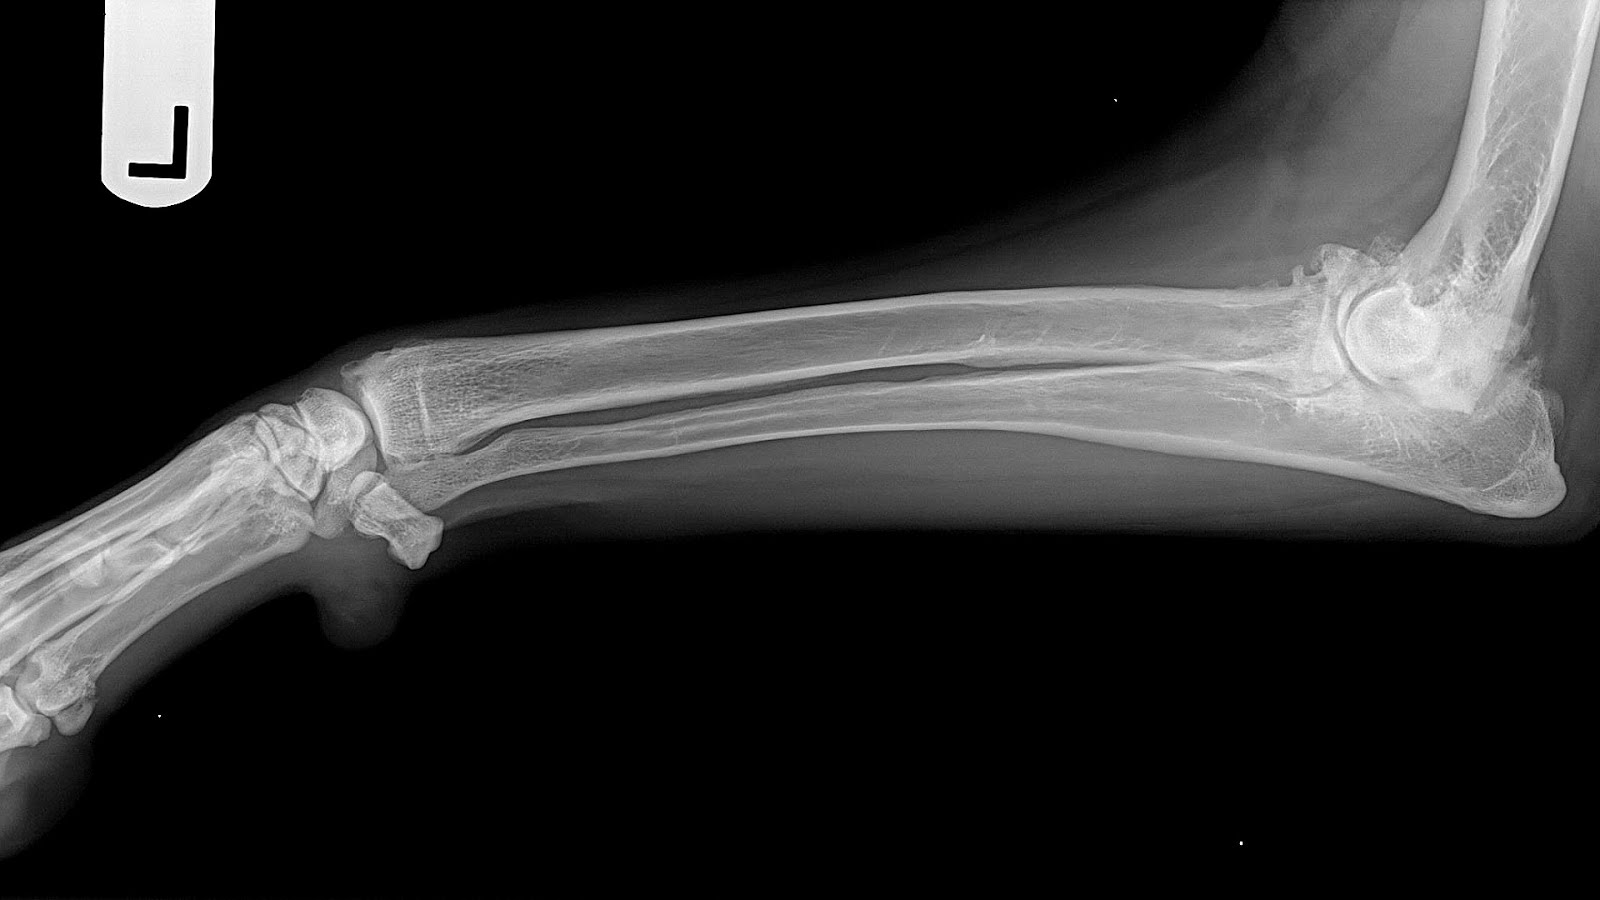

Инфекция кости у собаки - фото презентация